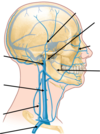

where does the venous blood supply drain into?

internal jugular vein

lable the diagram:

subclavian vein

external/ internal jugular vein

superficial temporal vein

maxillary vein

facial vein

inferior alveolar vein

retromandibular vein